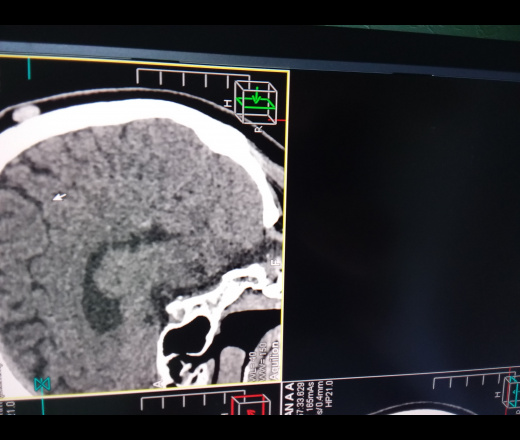

Код мкб 10 атерома головы

Код мкб 10 атерома головы 109 фото